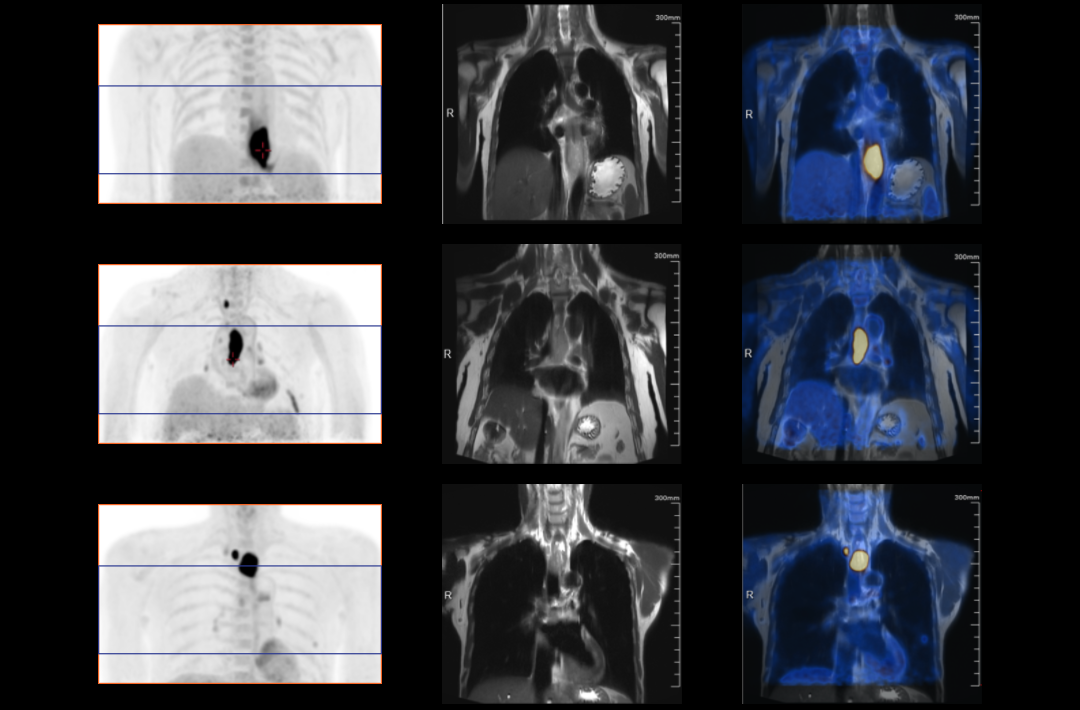

PET/MRは分子機能と構造画像を完全に結合し、腫瘍、心血管疾患、神経疾患、小児疾患、炎症性疾患の臨床診断に欠かせない手段として役立っています。

AFOVが、従来の20cm~25cmのPET装置と比較して、32cmの長尺AFOVであることにより、感度が向上するだけでなく、全身の主要臓器や転移が考えられる局所リンパ系において1ベッドポジションでがんのTNステージを実現することが可能となります。

従来、腫瘍系のPET/MR撮影には約35~50分かかっていました。長いAFOVは、PET/MRの腫瘍スキャン方式をさらに最適化することができます。局所PET/MRスキャン後に腫瘍の局所リンパ転移の有無に基づいて全身をスキャンするかどうかの判断を最適化でき、転移のない患者さまのスキャン時間を短縮できる可能性があります。

2019年8月、Peking Cancer Hospitalはユナイテッド イメージング ヘルスケアのPET/MRを導入し、長いAFOV下でのがんTNM病期決定の徹底的な探求と最適化を行いました。500例以上の様々な臓器のスキャンにより、長い AFOV PET/MRは1つのベッドポジションでのスキャン範囲を大幅に拡大し、がんTNMステージングの効率を向上させることができることが証明されました。

乳がん、食道がん、前立腺がんなどのTNMステージングを「時空間統合」ULTRA-clear TOF PET/MRの長軸視野で最適化した事例を紹介します。